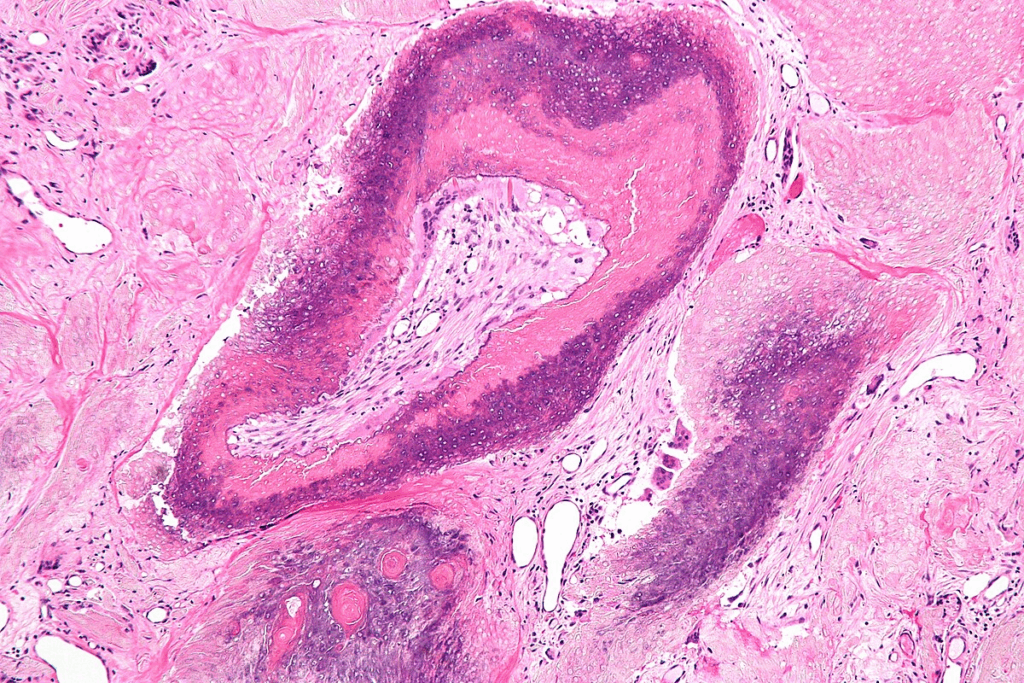

- Dermoid cysts: These are a type of pathological cyst that can contain tissue such as hair or teeth.